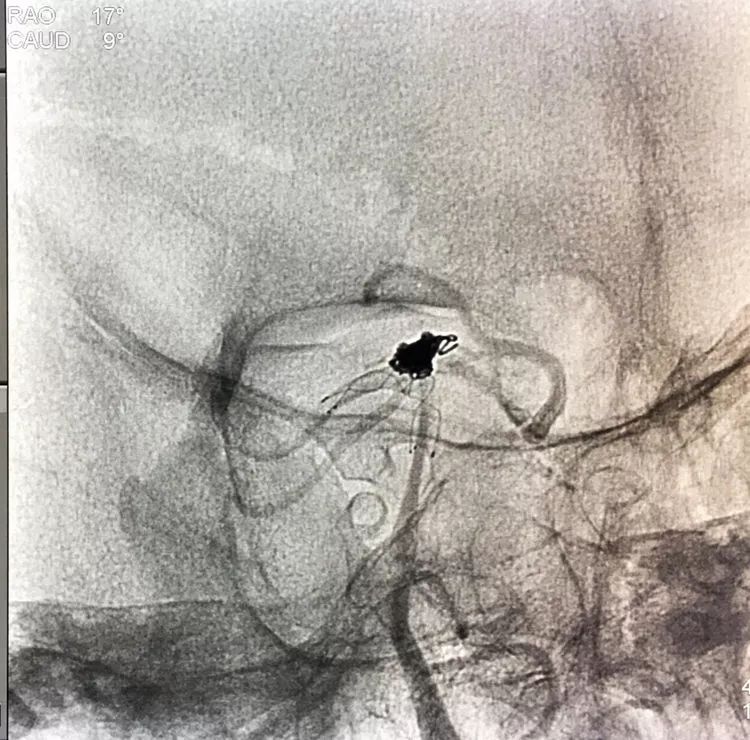

回到工作位造影,显示基底动脉顶端动脉瘤完全栓塞,基底动脉顶端四根血管畅通。

术后左椎动脉正位、侧位的造影和蒙片